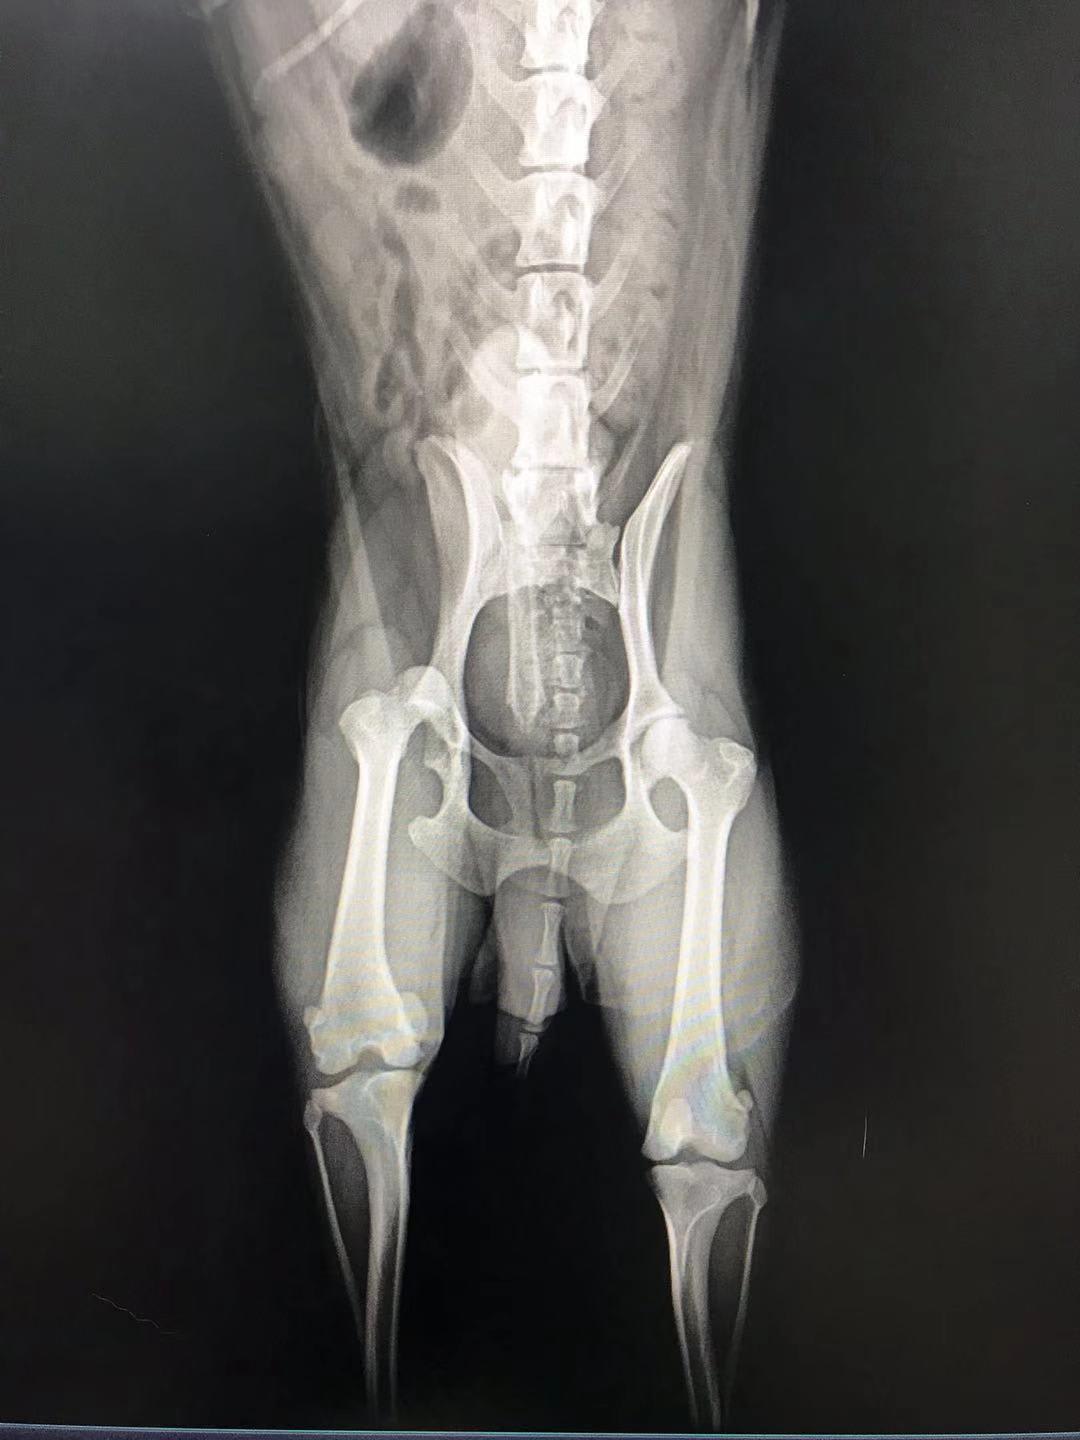

Hello, my dog is 8 years old now and he's facing two problems. The first one is patellar dislocation found two years ago and now it's the 3rd stage. Besides, he had a fight with a big dog 10 days ago, we took a X-ray today and found femoral ligament rupture. I'm wondering what treatment is best for him? Thank you very much.

Luxating patella is very common in small breed dogs. It can cause arthritis, and there is a surgery to address it if your vet tings Doudou is a good candidate. https://www.petcoach.co/article/luxating-patella/ As for the dislocated hip, he needs to surgery to replace it or to have the ball of the femur amputated (called a femoral head ostectomy - FHO). It sounds drastic, but is a very common surgery. The muscles of the hip/but will keep the joint in place, and, once healed, he should look completely normal when walking. You should discuss all available options with your vet, since the best one depends on the individual pet and their medical history. https://www.petcoach.co/article/5-most-common-orthopedic-injuries-in-dogs/